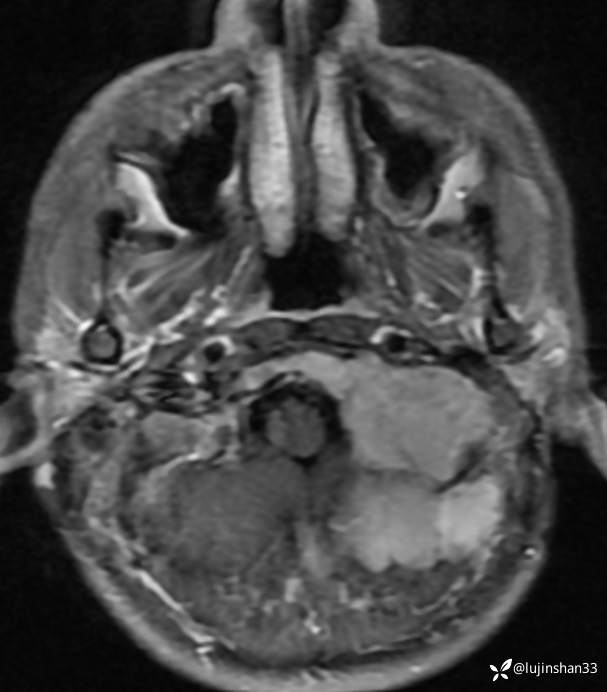

首次术前MRI

2019年2月首次手术后

首次手术有残留